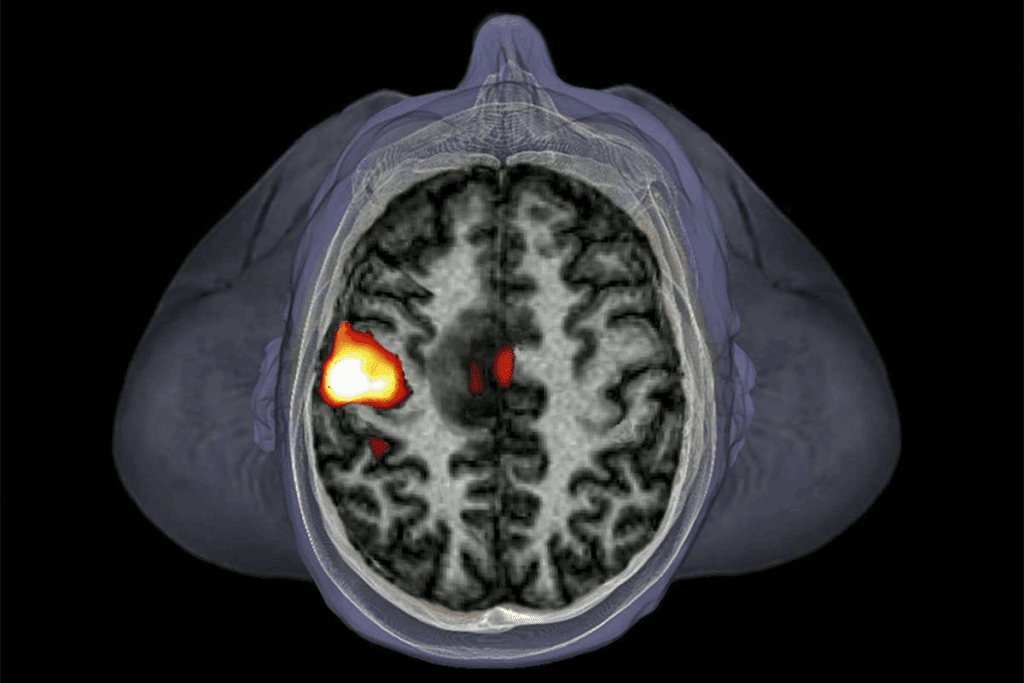

Imaging Techniques: MRI, CT, and PET Scans

Imaging is key in finding brain tumors. Magnetic Resonance Imaging (MRI) shows soft tissues well, perfect for tumors. Computed Tomography (CT) scans are fast but use radiation. Positron Emission Tomography (PET) scans show how tumors work, helping doctors decide on treatment.

But, these tools have downsides. MRI and CT scans are expensive and not everywhere. PET scans use radiation and are used in certain cases. Also, reading these images needs special skills, and results can vary.

Diagnosing brain tumors is complex. Both blood tests and MRI scans have their own strengths and weaknesses. It’s important to understand how they compare.

Diagnostic Accuracy Comparison

When it comes to finding brain tumors, accuracy is key. MRI scans are known for their detailed images. They help doctors see where and how big a tumor is. Blood tests, though newer, are also being used to find specific signs of tumors.

Comparative Accuracy: MRI scans are better at finding brain tumors than blood tests. But, blood tests are getting better thanks to new research and technology.

| Diagnostic Method | Sensitivity | Specificity |

| MRI | 85-90% | 90-95% |

| Blood Tests | 70-80% | 80-85% |